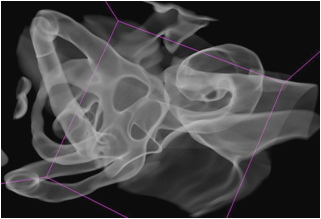

Die Schnittbild-Diagnostik mit MRT und CT hat sich in den letzten 10 Jahren revolutionär verändert. Insbesondere in der CT ist durch den Einsatz der Mehrschicht Spiral-CT Geräte die Erstellung von isotropen Volumen-Datensätzen zum Standard geworden. Mit modernen Workstations ist eine 3D-Nachverarbeitung dieser Datensätze möglich, die oft in hoher Qualität Zusatzaussagen ermöglicht. Während die einfachen Verfahren der multiplanaren Rekonstruktionen (MPR) und der Maximum Intensitäts Projektionen (MIP) relativ standardisierte Nachverarbeitungs-Algorithmen ermöglichen ist dies beim so genannten VolumeRendering (VR) noch relativ schwierig. Durch die fehlende Standardisierung ist der Einsatz dieser hoch potenten Methode in der Routinediagnostik zur Zeit nur eingeschränkt sinnvoll. Im Vortrag sollen die vorhandenen Methoden der 3D Nachverarbeitung sowie deren Einschränkungen und Probleme anhand von konkreten Beispielen aus der klinischen Praxis vermittelt werden.